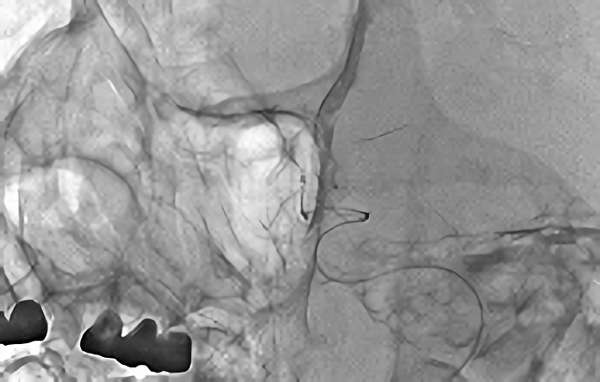

No.1631 手術中